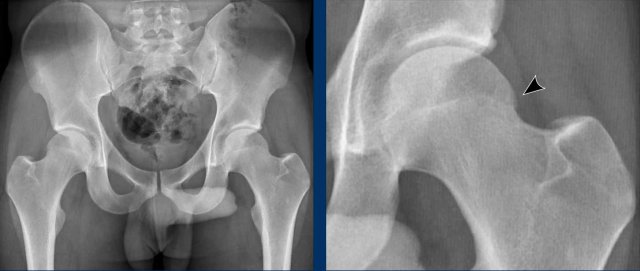

Subspine impingement

Subspine Impingement is a condition in which the anterior inferior iliac spine, also known as the subspine, impinges upon the femoral neck or head, especially during activities requiring deep hip flexion or rotation, such as sports or yoga.

These images are of a 23-year-old woman with a history of rheumatoid arthritis.

She presented with progressive pain in the right hip, particularly during flexion movements while practicing yoga.

Images

There is a variant with a low position of the inferior iliac spine (arrow).

This is another example of subspine impingement in a 28-year-old amateur football player who sustained acute trauma to the right hip region eight months ago.

Since then, he has experienced progressive hip complaints.

Physical examination reveals significantly reduced flexion, as well as decreased internal and external rotation.

Image

There is a typical avulsion injury of the anterior inferior iliac spine at the insertion of the rectus femoris tendon.

This has resulted in bony overgrowth, causing impingement. on the femoral head/neck region.

The ossification was surgically removed.